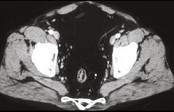

- 单项选择题男,41岁, 腹痛、腹泻、腹胀、脓血便、里急后重、疲乏无力,结合图像, 选择最可诊断  (    )

- A、溃疡性结肠炎

- B、结肠克罗恩病

- C、结肠结核

- D、假膜性肠炎

- E、结肠淋巴瘤